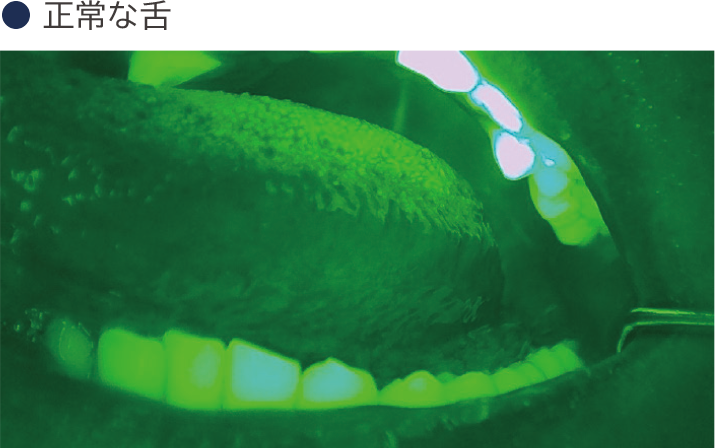

当院では、通常の診察に加えて、口腔内蛍光装置(イルミスキャン)を使用したスクリーニングも行っています。特に、たばこを吸う方、お酒をよく飲む方、口の中に異常を感じる方におすすめです。

口腔がん検診は、口の中にがんや将来がんになる可能性のある異常がないかをチェックするための検査です。